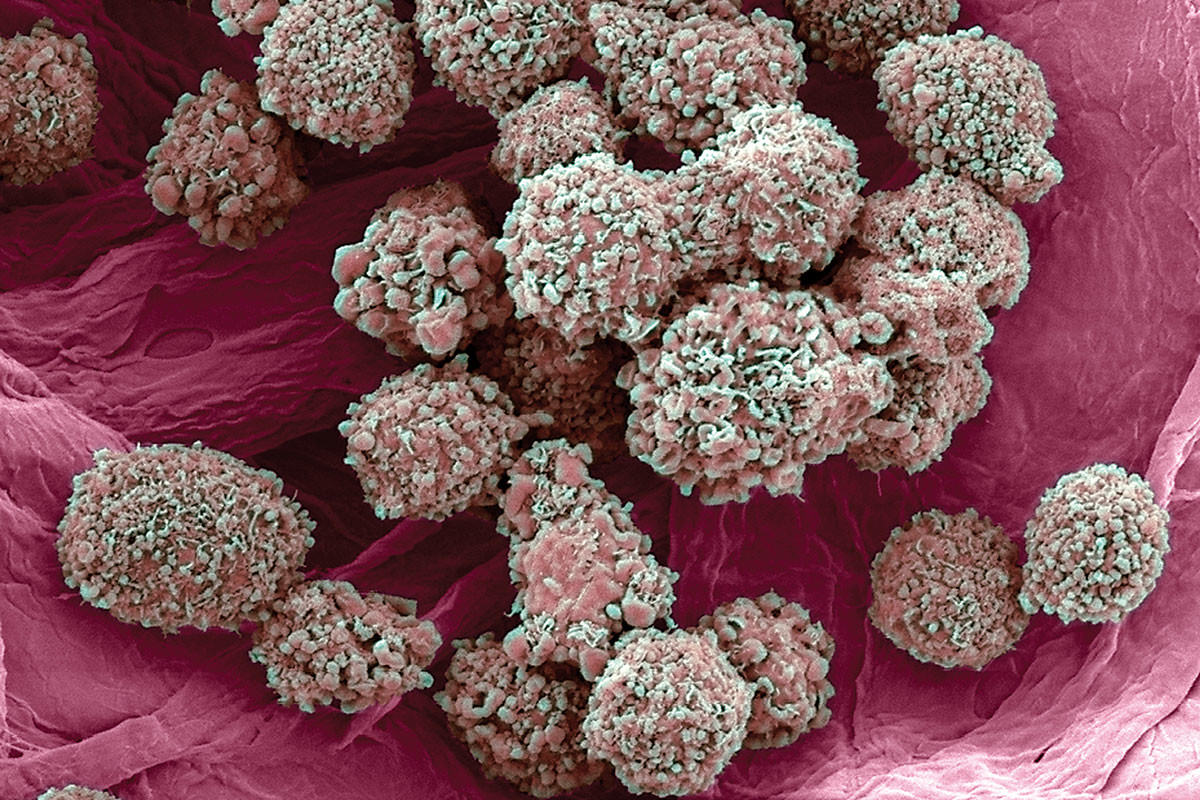

Раковая шишка – это заболевание, которое поражает кожу и слизистые оболочки. Она может возникнуть в различных частях тела и иметь различные внешние проявления. В данной статье мы представляем вам многочисленные фотографии раковых шишек, чтобы вы могли узнать, как они выглядят.

Одной из наиболее распространенных локализаций раковых шишек является лицо. На фото вы можете увидеть различные типы раковых шишек, такие как базалиома, плоскоклеточный рак и меланома. Обратите внимание на характерные признаки каждого типа раковой шишки, такие как изменение цвета, формы и размера.